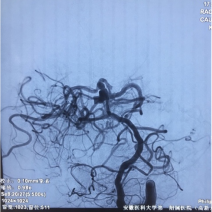

直升机返回高新院区后,早已就位的神经外科、急诊科医务人员迅速开通绿色通道,积极完善术前相关检查及术前准备。并于当日在麻醉科、影像科介入导管室及急诊ICU等多学科协作下,急诊全麻下行全脑血管造影及颅内动脉瘤栓塞术。

由于该患者系基底动脉远端分叶状动脉瘤,位置特殊,形态复杂,累及多根重要血管。神经外科脑血管病团队,仔细分析病情后,采用支架辅助及双微导管技术,成功对该动脉瘤实施了致密栓塞,杜绝了动脉瘤再次破裂出血的风险。